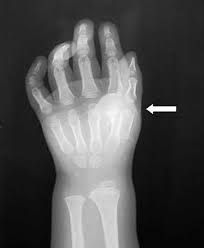

Esta enfermedad es una osificación progresiva de los músculos y huesos. No tiene cura y la idea es saber más sobre ella, nacen huesos en cualquier zona del cuerpo, (músculos, tendones, etc.) y éstos no son operables, si no, crecen más fuertes.